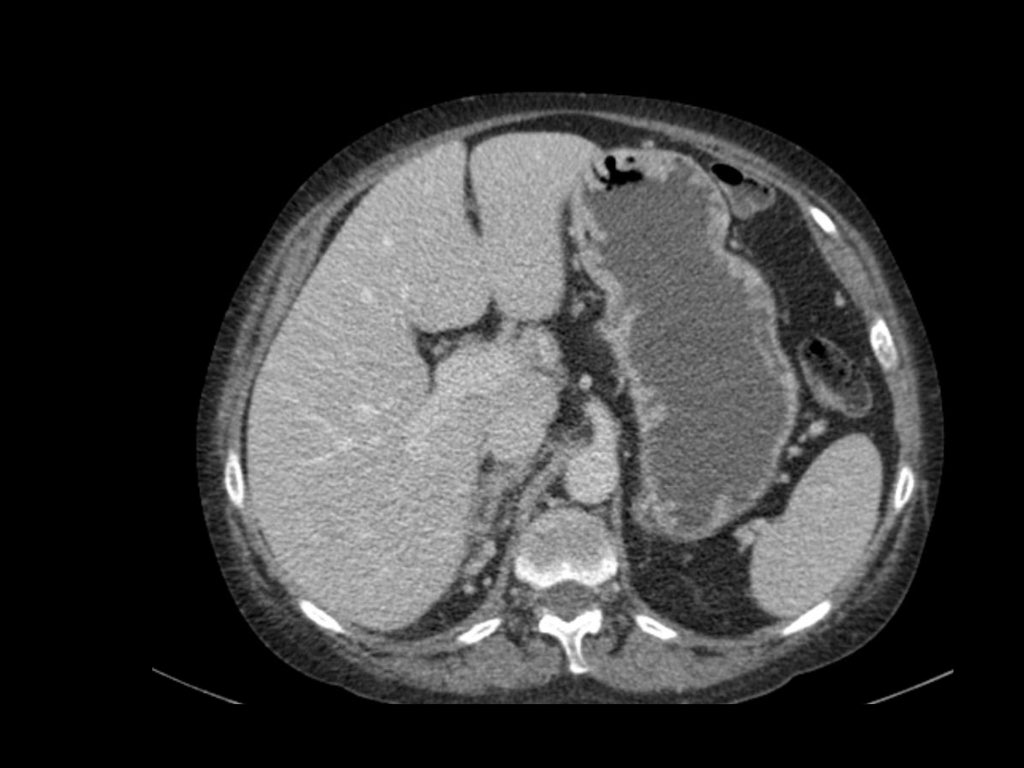

Đặc điểm điển hình của ung thư biểu mô tế bào sáng là ngấm thuốc mạnh trong thì vỏ-tủy (corticomedullary phase).

Điều này có thể khó đánh giá khi tổn thương nhỏ và nằm ở vỏ thận, vốn cũng ngấm thuốc mạnh.

Do đó, thì thận (nephrogenic phase) là thì nhạy cảm nhất để phát hiện các tổn thương này, vì nhu mô thận ngấm thuốc đồng nhất và đậm hơn so với khối u (hình minh họa).

Tổn thương thâm nhiễm ở cực trên thận phải, hầu như không thấy trên ảnh không tiêm thuốc (bên trái), thấy rõ ràng ở thì thận (bên phải). Giải phẫu bệnh xác nhận RCC tế bào sáng

Trong số tất cả các RCC tế bào sáng, khoảng 5% có kiểu tăng trưởng thâm nhiễm.

Mặc dù đây chỉ là một tỷ lệ nhỏ trong số các RCC, nhưng tần suất chung của RCC khiến đây trở thành một chẩn đoán phân biệt quan trọng đối với tổn thương thâm nhiễm dạng hình đậu (bean-type).

RCC thâm nhiễm có tính chất xâm lấn cao và tăng sinh mạch máu.

Tổn thương làm thay đổi cấu trúc nội tại của thận nhưng vẫn bảo tồn đường bờ thận. Các bất thường hệ thống đài bể thận có thể tương tự như những gì thấy trong ung thư biểu mô tế bào chuyển tiếp (transitional cell carcinoma).